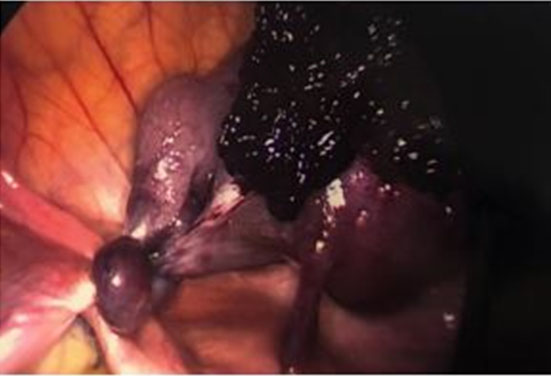

Based on the abdominal exam findings and hydrosalpinx noted on imaging, the decision was made to proceed with diagnostic laparoscopy. On laparoscopic survey, the bilateral ovaries and the right fallopian tube appeared normal. The left fallopian tube was found to be torsed three times, dusky in appearance, enlarged, and distended with old blood (Figure 2). After detorsion of the tube, there was no improvement in its appearance, and the decision was made to proceed with left salpingectomy. The procedure was uncomplicated with an estimated blood loss of less than 10 mL. The patient did well postoperatively and was discharged on postoperative day 0. The left fallopian tube was sent to pathology and the final pathology diagnosis confirmed hematosalpinx with torsion.

Figure 2: Torsed left fallopian tube viewed via laparoscopy (Case 1).